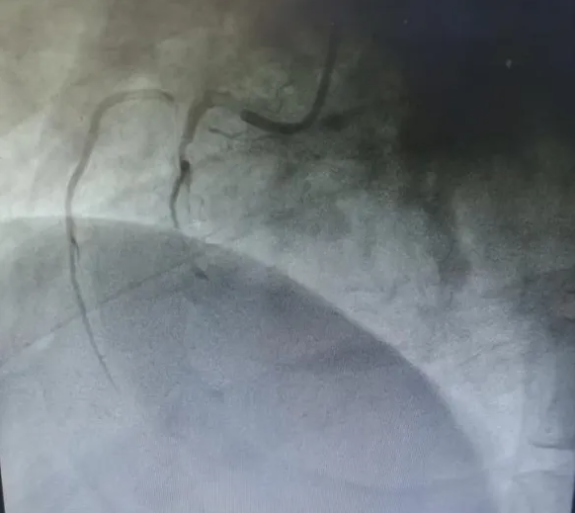

?复查心电图明确诊断为急性下壁心肌梗死,病情极其凶险。冠脉造影结果显示:冠脉三支严重病变,其中右冠状动脉中段急性完全闭塞,伴大量血栓影,合并右冠自发性夹层,属于极高危复杂病变,随时可能再次发生恶性心律失常、心源性休克甚至猝死。

(术前冠脉造影)